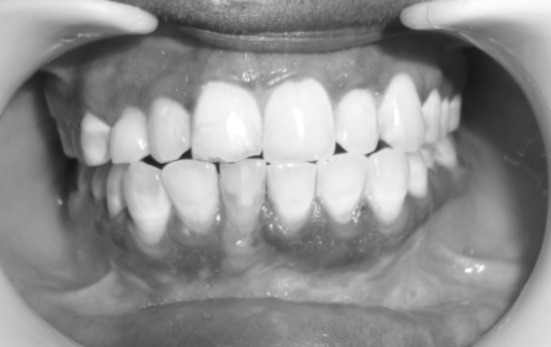

Fig. 1.

Deranged occlusion

6 month post operative occlusion

Fig. 9.